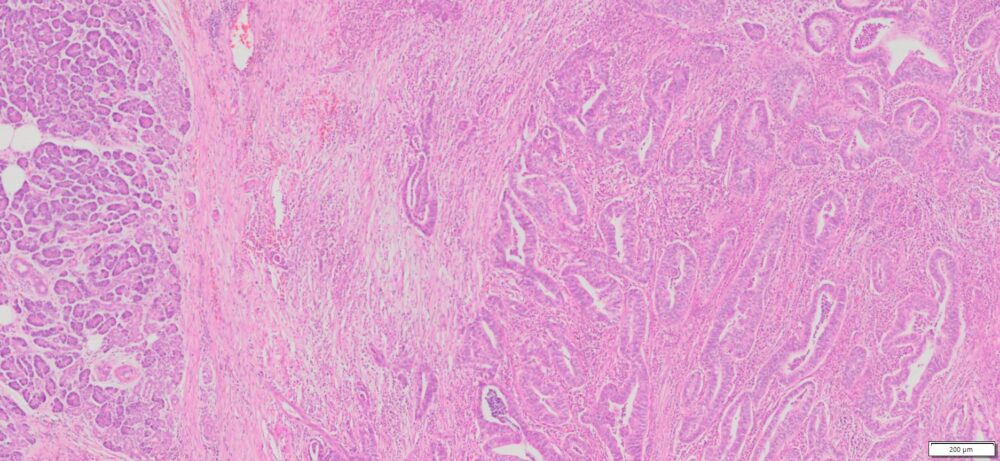

Description

| Tissue | Pathology Diagnosis | Gender/Age (year) | Tissue of Origin | % Tumor area | Tumor Grade | TMN Stage | IHC Data |

| Human Pancreas Cancer | Pancreatic ductal adenocarcinoma | Female/76 | Head of Pancreas | 75% | II | PT2PN1Mx | NA |